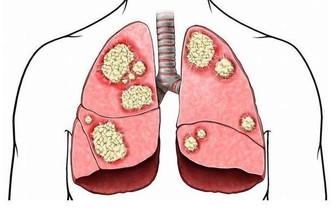

2. 咳嗽

咳嗽是呼吸系統中最常見的症狀之一,是人體的一種保護性措施,對機體是有益的。當呼吸道黏膜受到異物、炎症、分泌物或過敏性因素等刺激時,即反射性地引起咳嗽,有助於消除自外界侵入呼吸道的異物或分泌物、消除呼吸道刺激因子。

這樣咳嗽是壞事

所以,出現咳嗽症狀時,做好保暖的同時,還需補充大量的水分,同時避免胡椒、洋蔥等辛辣食物刺激呼吸道。如頻繁咳嗽還伴有發燒、胸痛、體重減輕等症狀時,就立即就醫。